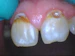

A new portable electronic cavity detection system from Ortek Therapeutics Inc. can spot dental caries before the lesions can be seen on x-rays, allowing time for minimally invasive dental treatment.

A new portable dental device—Ortek ECD—can detect dental caries before the lesions can be seen on x-rays. The electronic cavity detection system from Ortek Therapeutics Inc. was developed and tested at Stony Brook University School of Dental Medicine and is FDA-approved for professional use only.